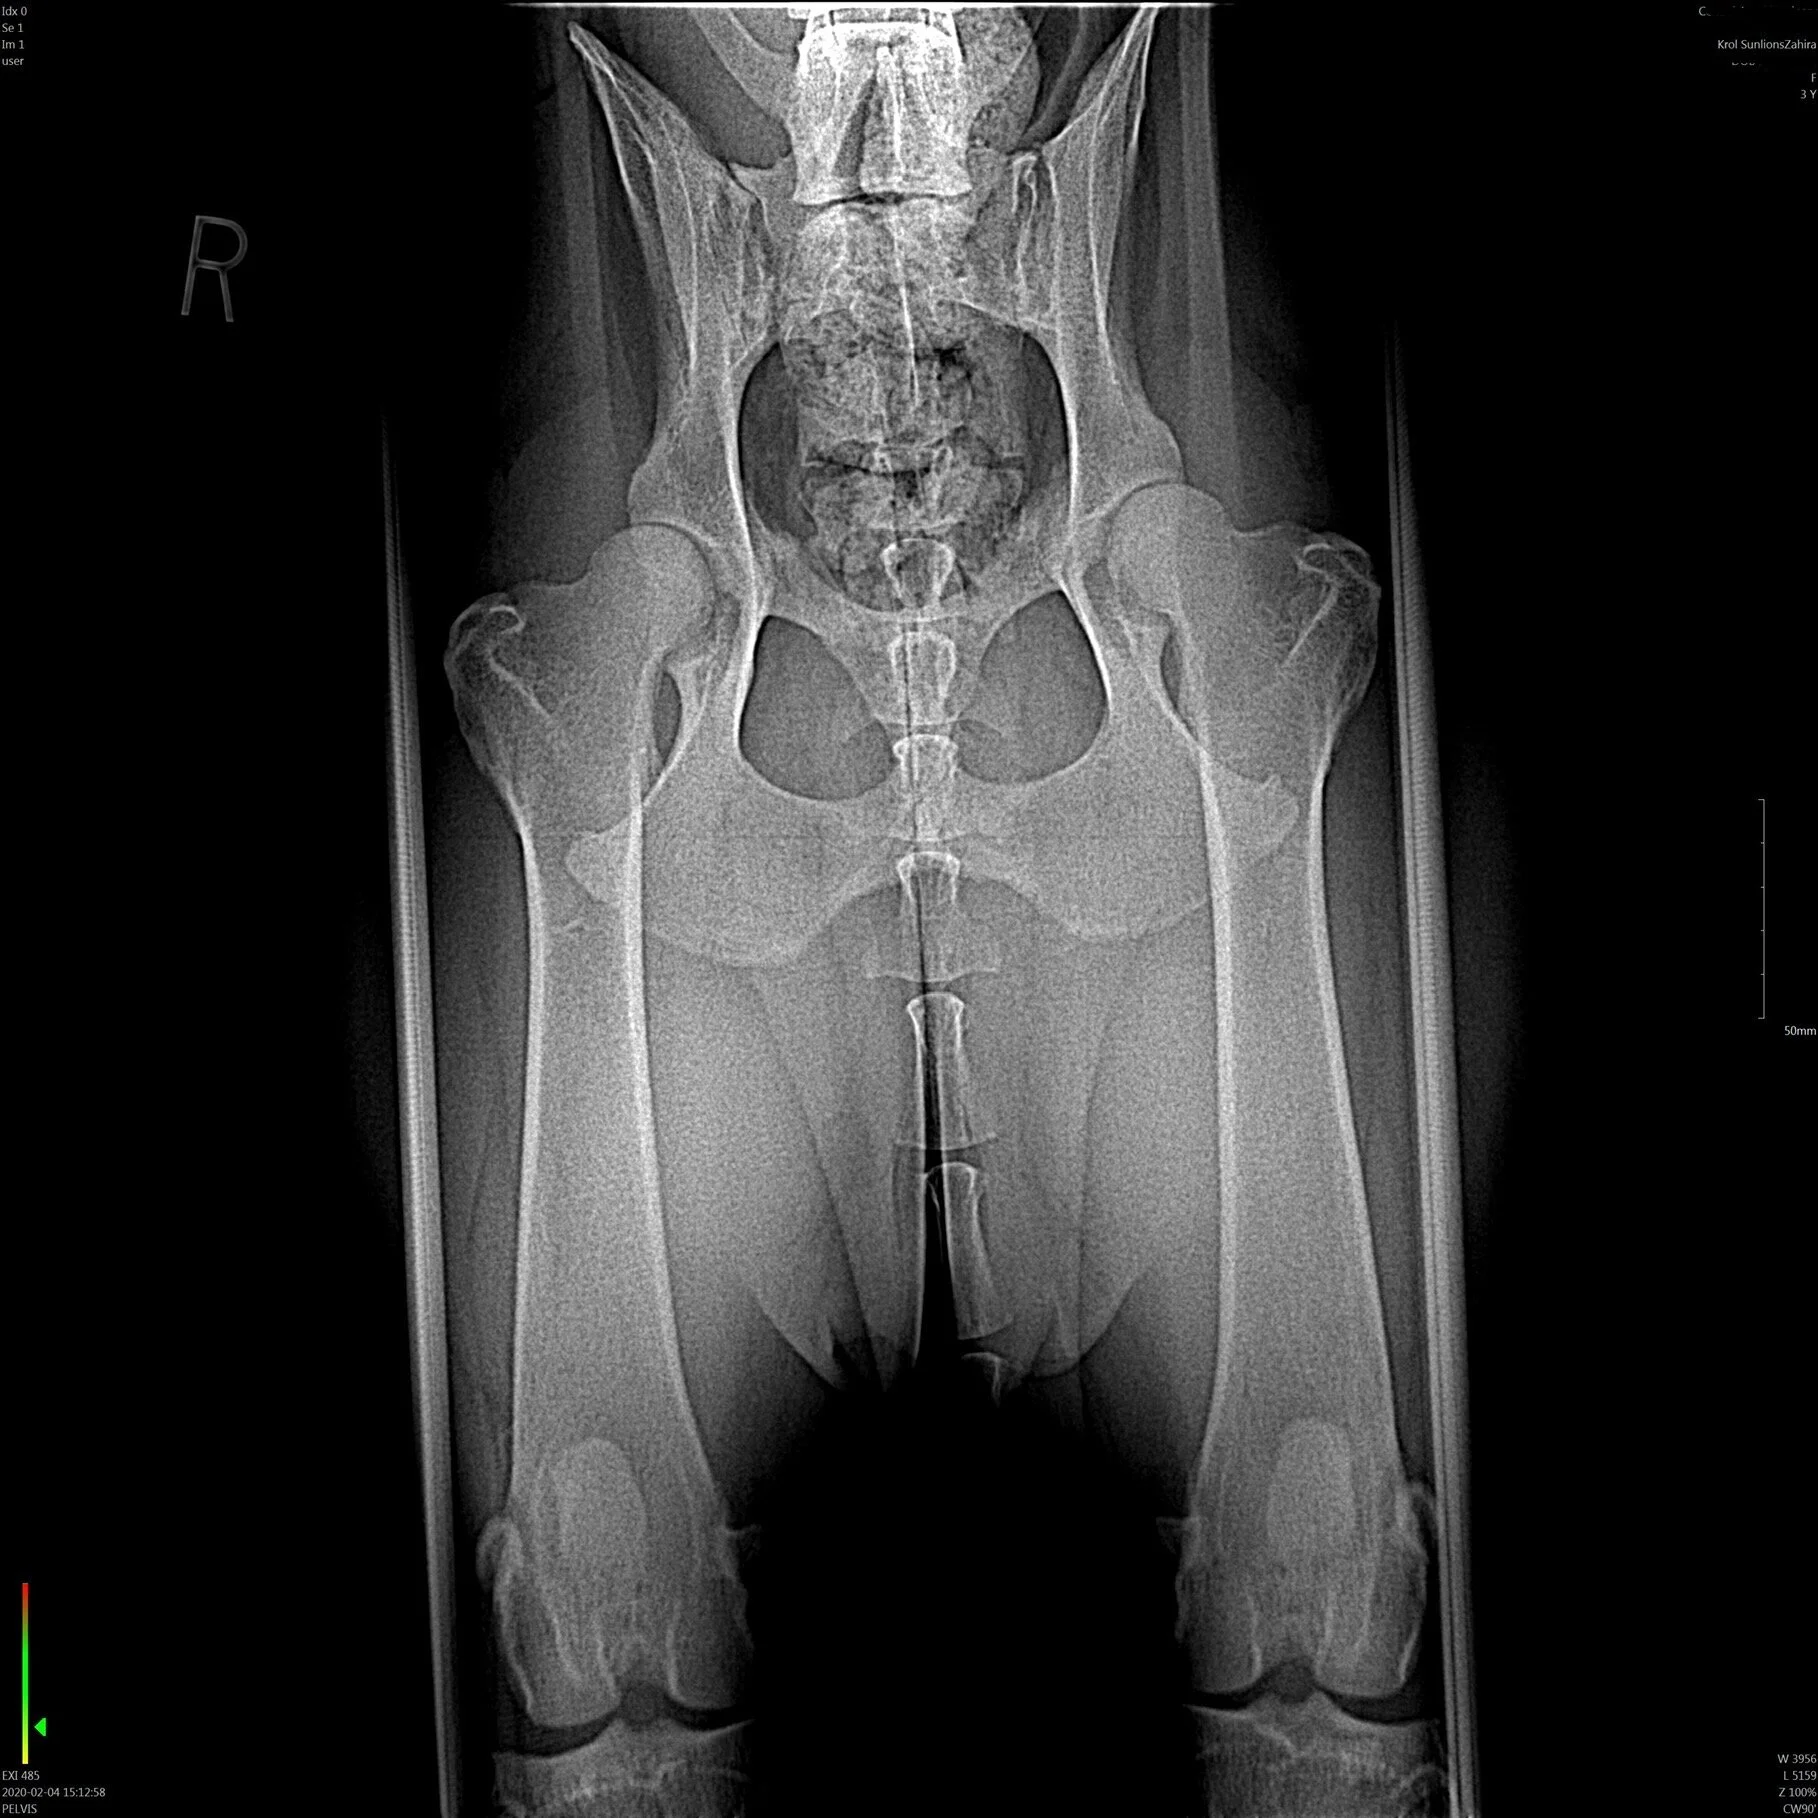

Zahira’s hips at 3.5 years old. OFA EXCELLENT